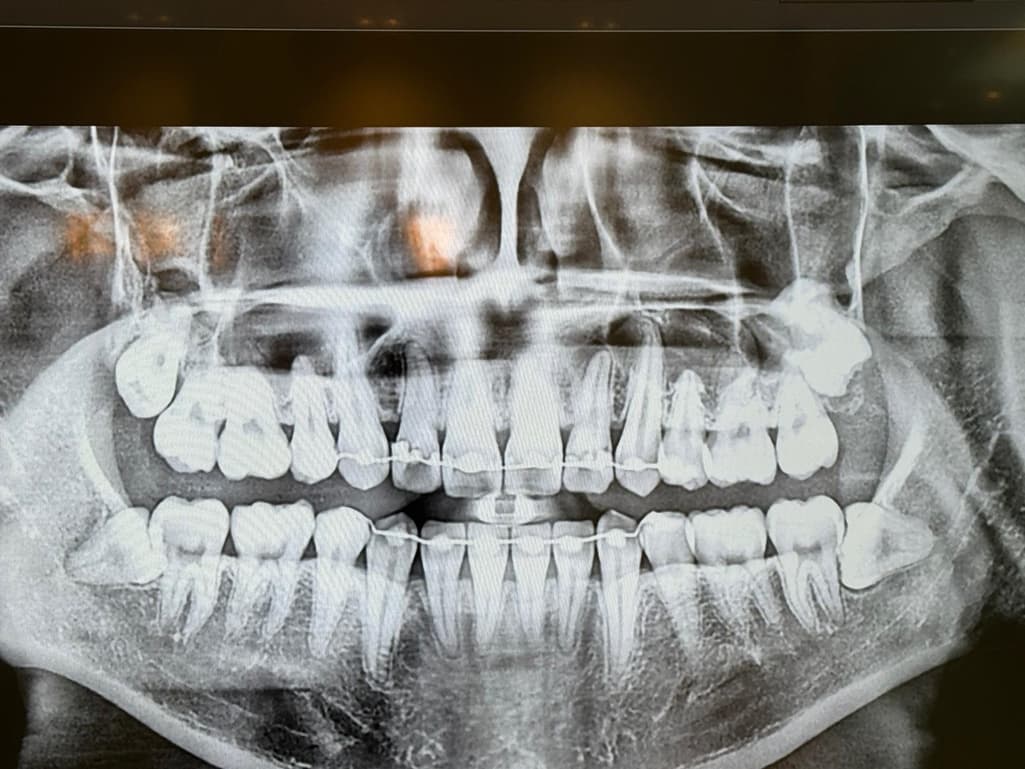

사진은 24년1월 24년 12월 25년 5월 순입니다

• 3번 째 사진

사진상으로는 염증이 명백히 보이지만 증상이 없다면 일단 지켜보는 것도 괜찮을 것 같습니다.

엑스레이 상으로는 크게 염증이 커지거나 그렇진 않은거 같습니다. 증상이 없다면 정기적으로 치과를 다니시면서 관리를 받으시면될것같습니다.

파노라마 사진상으로 측은단 부위에 병소가 보이고 있습니다. 정확한 확인을 위해서는 CT 촬영을 해보는 것이 좋을 것으로 생각되며 치근단 질환이 생겼다는 것은 근관 내가 이미 감염이 되었다는 것이기 때문에 치근단 질환이 있다면 신경 치료를 해줘야 합니다. 그렇지 않다면 주변에 있는 치조골이 손상되어 나중에는 치아를 손실 할 수도 있습니다.